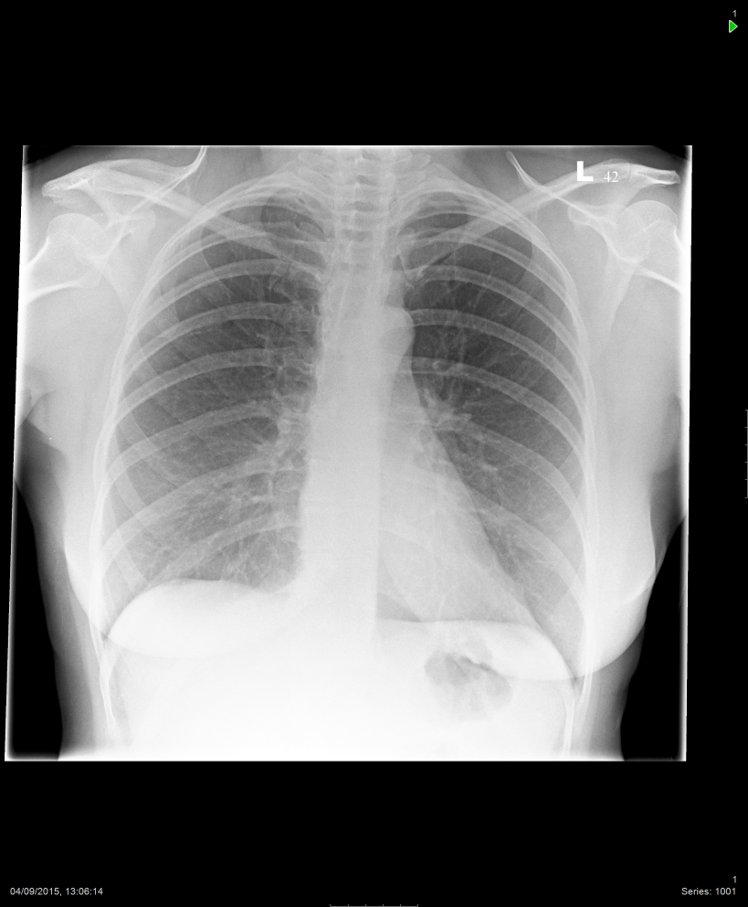

Tachy, CP. ?pulmonary oedema

• Normal variant (1)

• Congenital dextrocardia / situs invertus (2)